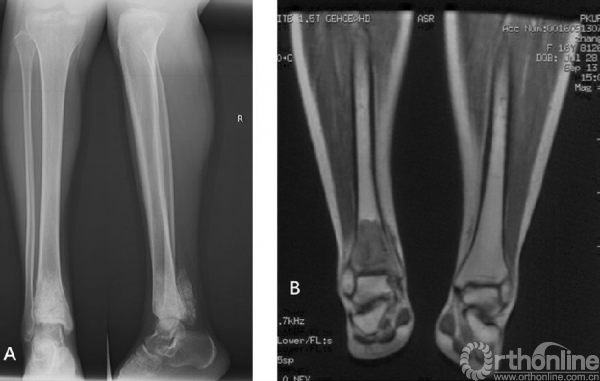

图2女性/16岁,右胫骨下端骨肉瘤。A术前X光片,右胫骨下端骨肉瘤,后方软组织包块影伴肿瘤性成骨。B化疗后MRI显示胫骨下端异常信号影。C术中完整切除胫骨远端肿瘤后刮除髓腔内肿瘤、65℃ 20%高渗盐水灭活30分钟后原位回植、对侧自体腓骨置于髓腔中心、钢板内固定、LARS韧带重建内踝软组织、下胫腓关节融合。D术后即刻X光片。E术后6个月X光片显示截骨面已模糊。F术后踝关节功能良好,7个月后无需支具辅助可正常行走。